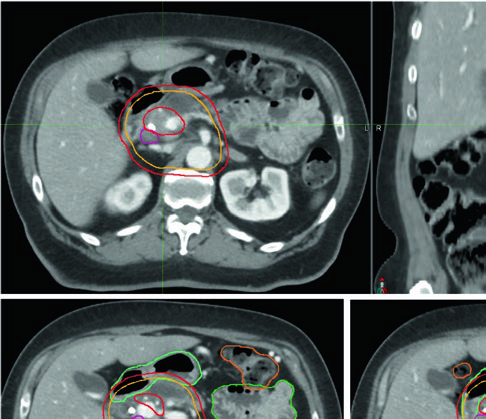

Volúmenes blanco en el escenario neoadyuvante (borderline resecable)

El tratamiento preoperatorio de enfermedad borderline resecable o resecable de alto riesgo utiliza dosis más bajas y, por tanto, tecnología menos compleja. Sin embargo, los márgenes deben ser suficientemente generosos para englobar toda la enfermedad microscópica y la extensión radiográficamente oculta a lo largo de la vasculatura.

Definición de volúmenes neoadyuvantes

| Volumen | Definición y descripción |

|---|---|

| GTV | Toda enfermedad macroscópica en imagen, incluyendo el tumor primario (típicamente hipointenso), con atención especial a la extensión a lo largo de los vasos y todos los ganglios sospechosos |

| ITV (opcional) | Si se utiliza enfoque ITV, delinear el GTV en todas las fases del 4D-CT |

| CTV | Expansión uniforme de al menos 1 cm sobre toda la enfermedad macroscópica + cobertura de cadenas del tronco celíaco (CA) y arteria mesentérica superior (AMS) + margen adicional a lo largo de vasos en caso de incertidumbre + cobertura del hilio esplénico (lesiones de cuerpo/cola) + cobertura opcional de porta hepatis (lesiones de cabeza) |

| PTV | Margen basado en técnica de control de movimiento, mínimo 0,5 cm. Sin ITV y en respiración libre, expansión de 1–1,5 cm en dirección craneocaudal |

Fuente: Target Volume Delineation and Field Setup, 2nd Edition (Table 16.1)